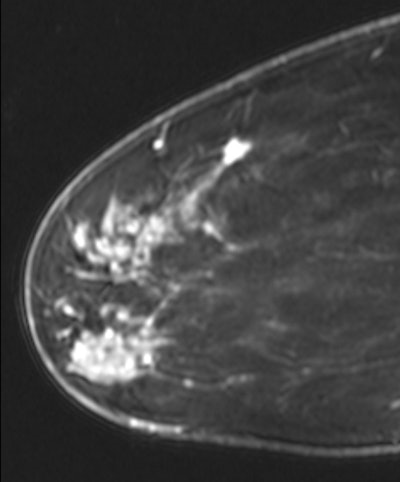

MRI shows a new lesion found superiorly in the breast. The lesion was subsequently biopsied, revealing another focus of invasive ductal carcinoma.

MRI shows a new lesion found superiorly in the breast. The lesion was subsequently biopsied, revealing another focus of invasive ductal carcinoma.Overall, among the 243 initial patients, 10 women chose not to undergo surgical excision. As for the remaining 233 individuals, MRI changed surgical management in 111 cases (48%), and positive lymph nodes were found among 55 patients (23%).